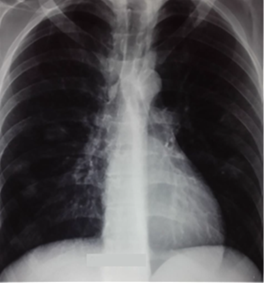

The

radiological evolution was favorable (figure 4) but a widespread

thrombosis of the right jugular vein persisted.

Figure 4: la radiographie thoracique à la sortie